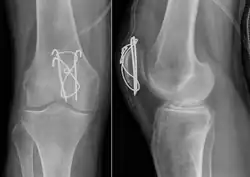

-

Transverse fracture of patella -

Most patella fractures are transverse or comminuted, hence the quadriceps mechanism is disrupted and they are treated by a combination of wires in a tension band construct. This unites the fractured bones, reconstructing the straightening mechanism of the leg.[5][6]